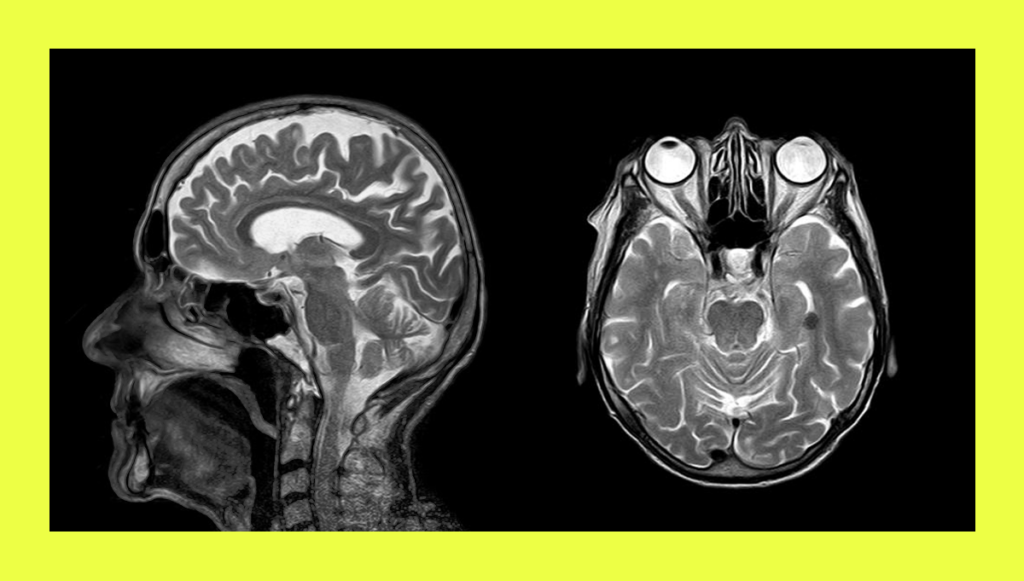

В 2019 году Алик получил травму головы. В больнице ему диагностировали отёк мозга и через некоторое время провели трепанацию черепа (в распоряжении редакции есть выписной эпикриз).

Из-за травмы у него отнялась левая рука, а после операции стали происходить эпилептические приступы — они случаются и по сей день, говорит Мира. Также в больнице у Алика были истерики, он агрессивно себя вёл и с трудом подпускал к себе врачей.

В ноябре этого года Алику предстояла операция по установке металлической пластины в череп. Но состоится ли она теперь — неизвестно. 24 сентября Алик получил повестку от военкомата.